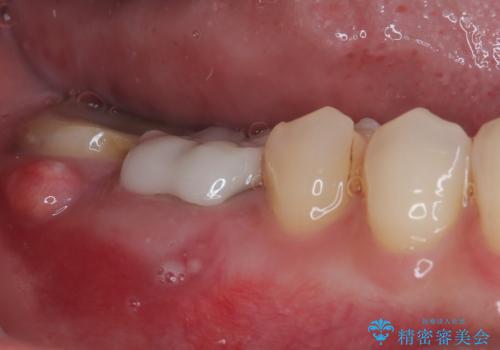

抜歯後も膿の出口が消えず、一番奥の歯を診察したところ神経組織の反応がなかったため、根管治療を行うこととしました。

再度の歯を根管治療したため、抜歯した部位の補綴治療は、強度の問題からブリッジよりもインプラントをおすすめしましたが、患者様希望によりブリッジを選択しました。

一番奥の歯は歯肉から露出している高さが少なく、クラウンを装着する不十分であったため、歯冠長延長術を行うこととしました。